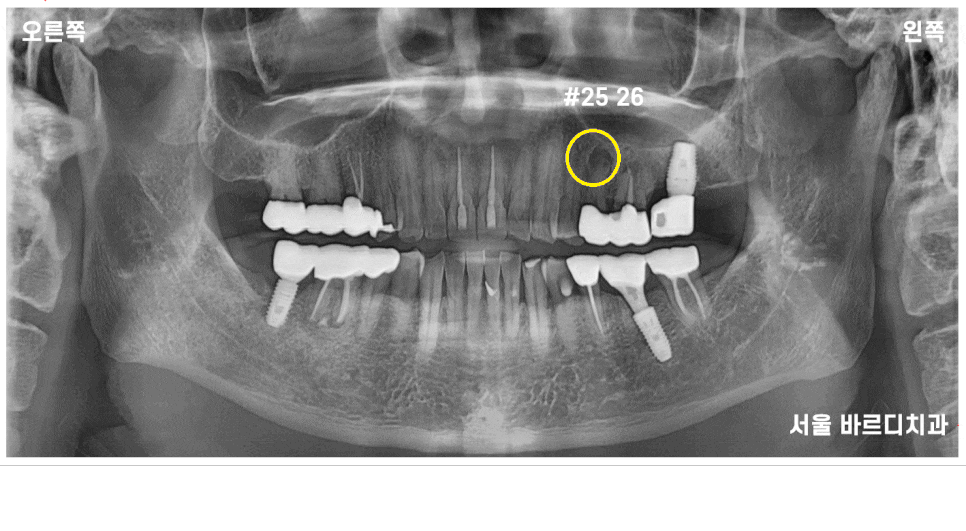

23.07.06

전반적으로 잇몸이 조금씩 내려간 부분은 있었지만

제일 문제가 되는 부분은 왼쪽 위였습니다.

파노라마 전체 사진상으로도

좋아 보이지 않아

자세히 관찰할 수 있는

작은 x-ray를 한 장 더 찍어 보았습니다.

노랗게 동그라미 친 부분이

치아 뿌리 끝에 염증을 의미합니다.

이미 치료를 받은 치아에 염증이 생겨

주변 뼈를 녹이고 있는 상태

옆에 치아도 좋지 않은 것은 마찬가지였습니다.